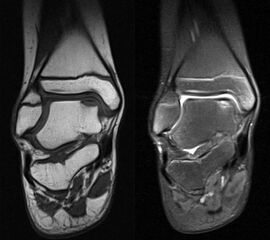

MRT

Die Kernspintomographie hat ihre Stärke in der Darstellung von Weichteilverletzungen. Insbesondere Verletzungen der Wachstumsfuge, des Periosts und der Bänder lassen sich gut visualisieren. Nachteilig ist die Untersuchungsdauer von 20-30 Minuten. Bleibt das Kind während dieser Zeit nicht ruhig liegen, kommt es zu Bewegungsartefakten, welche die Beurteilbarkeit der Bilder beeinträchtigen.